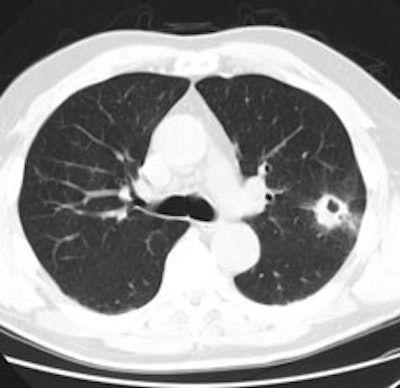

|

Unsuspected bone metastases: The patient shown below had a cavitary left lung non-small cell lung cancer. There was no uptake of tracer within the aortopulmonary window lymph nodes detected on CT to suggest metastases, however, unsuspected bone metastases were found in the left anterior 4th rib (black arrow) and lumbar spine (red arrows- not included in staging lung CT scan). The presence of bone metastases significantly alters patient prognosis and management. PET imaging provides a rapid whole body survey for the detection of unsuspected metastatic disease. |